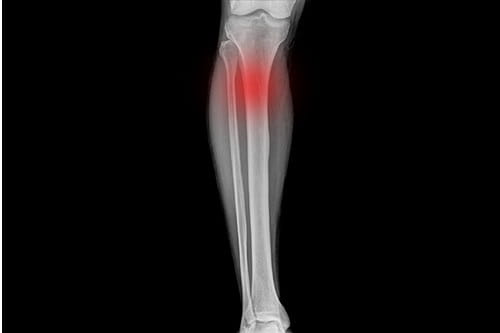

En stressfraktur är en liten spricka i benet som uppstår till följd av upprepad överbelastning över tid, snarare än genom ett plötsligt trauma. När vi springer uppstår ständigt mikroskopiska skador i skelettet, en process som normalt gör benet starkare när kroppen får tid att reparera sig under vila.

Om belastningen ökar för snabbt hinner dock inte återhämtningen med, och de små skadorna ackumuleras tills en faktisk fraktur bildas i benvävnaden. Det är en tydlig varningssignal från kroppen att din löpning sliter för mycket på skelettet.

Skelettet är levande vävnad som ständigt bryts ner och byggs upp i en process som kallas remodellering. Problemet uppstår när nedbrytningen sker snabbare än uppbyggnaden. De vanligaste platserna för en stressfraktur hos löpare är skenbenet (tibia) och mellanfotsbenen (metatarsalerna).